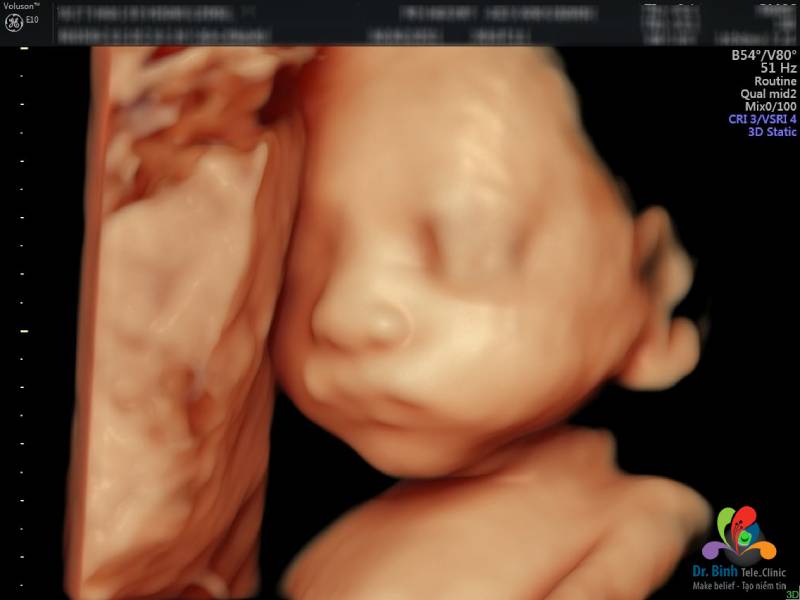

Siêu âm 4D là kỹ thuật tái tạo hình ảnh thai nhi có trong tử cung của mẹ qua sóng âm. So với các phương pháp siêu âm cũ 2D, 3D, phương pháp siêu âm thai 4D giúp mẹ bầu và bác sĩ có thể quan sát bé ở nhiều góc độ, bao gồm cả các chuyển động: đạp, mút ngón tay, ngáp, cười...

Siêu âm 4 chiều, kỹ thuật siêu âm hiện đại có thể quan sát hình ảnh của bé qua nhiều góc độ khác nhau